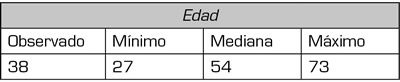

Se identificaron 45 pacientes llevados a bloqueo de nervios cluneales con diagnóstico de dolor lumbar crónico con signos y/o síntomas de clunealgía, cumpliendo los criterios de inclusión. Los síntomas más frecuentes fueron el dolor neuropático irradiado a miembros inferiores en el 57 % (n = 21) y el dolor lumbar en el 36 % (n = 13) se obtuvieron datos sociodemográficos descritos en Tabla I y II. Hubo pérdida de seguimiento de 11 pacientes posterior al procedimiento (Figura 2).

Fig. 2. Gráfica selección de pacientes. Se identificaron 49 pacientes. De estos, de 11 no se logró contacto efectivo y hubo pérdida de seguimiento posterior al procedimiento.